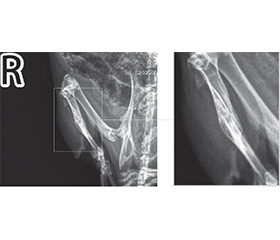

Background. At the present stage, experimental studies and clinical observations are continuing to develop new treatment methods for improvement of bone fracture healing. In the era of increasing incidence of primary malignant and metastatic bone tumors, as well as in times of traumatic epidemics during the war, studying the possibilities of influencing the course of bone repair in order to accelerate or improve it is a justified direction of experimental research. Objective: to study the influence of modulating factors — infrared laser radiation, calcitonin and probiotic based on Bifidobacterium animalis — on the healing of a bone defect in an in vivo experiment. Materials and methods. Reparative osteogenesis was studied in 32 animals (Wistar rats) whose tibia were injured with a dental drill using ketamine anesthesia. The influence of modulating factors on the formation of bone callus was assessed by studying the injured limbs of animals using the Toshiba Radrex X-ray diagnostic system, with a power of 80 kW, a radiation dose during digital radiography of 0.03 mSv, ventrodorsal positioning (on the stomach, back up), as well as right lateral (side views). Results. The study showed that the formation of bone callus under the influence of the laser is active, but nonlinear and not always symmetrical, which is in line with the results obtained in other studies. Instead, this work for the first time paid attention to the study of the combined effect of several modulating factors on reparative osteogenesis, namely laser irradiation, calcitonin and probiotic. It should be noted that we observed the maximum stimulating effect on the formation of bone callus in experimental animals in the laser + calcitonin group, which can even be characterized as excessive reparative activity of bone tissue. On the other hand, in the groups where a probiotic was present, reparative osteogenesis in rats proceeded more harmoniously, demonstrating better radiological results, such as in the calcitonin + probiotic group and especially in the group where the B.animalis preparation was combined with laser and calcitonin administration. It can be reasonably assumed that the inherent ability of B.animalis to normalize calcium metabolism creates conditions for reparative osteogenesis, as close as possible to the physiological scenario. Conclusions. The combination of calcitonin with a probiotic, as well as laser irradiation with calcitonin and a probiotic promoted harmonious reparative osteogenesis, which is confirmed by the corresponding radiological picture. The ability of B.animalis to reduce the intensity of systemic inflammation, to modulate calcium absorption from the intestine and influence its metabolic pathways may be a prerequisite for achieving complete bone repair.